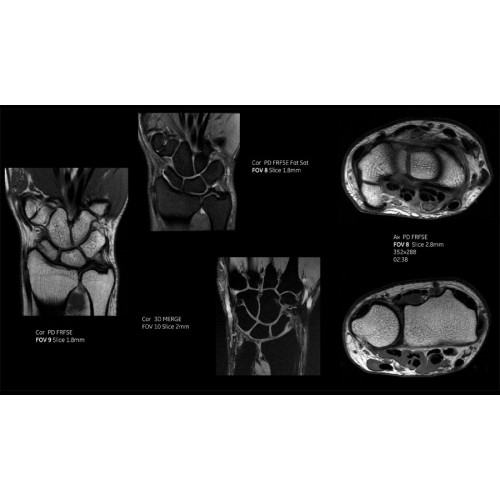

МРТ аппарат GE SIGNA Voyager 1.5T позволяет проводить полный спектр магнитно-резонансных исследований, включая нейровизуализацию, исследования опорно-двигательного аппарата, органов брюшной полости и малого таза, а также специализированные кардиологические программы.

• Ортопедия и травматология